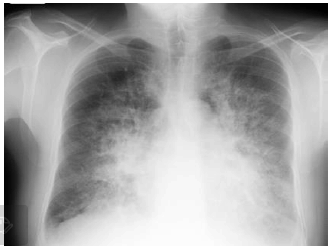

Paciente de 66 anos, do sexo masculino, com antecedente de hipertensão, dá entrada no Pronto Socorro com quadro de dispneia de instalação em horas, após comparecer a churrasco.

Admitido prontamente na UTI, apresenta os seguintes sinais vitais: FC 120, PA 210x120, FR 46, SatO2 90% em máscara de O2. Apresenta, ainda, a seguinte radiografia de tórax:

O paciente foi intubado, iniciada ventilação mecânica invasiva com os seguintes parâmetros em pressão controlada: PEEP 10, PC 15, FR 25, FiO2 100%. Coletada gasometria arterial com o seguinte resultado: pH 7,4, pCO2 40, HCO3 24, pO2 105, SatO2 98%. Tendo em vista os critérios de Berlin para diagnóstico de Síndrome do Desconforto Respiratório do Adulto, esse paciente não se encaixa no seguinte critério: